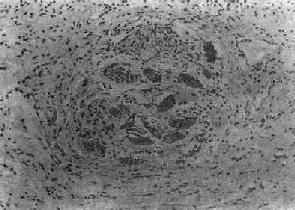

(2)慢性虫卵结节:急性虫卵结节经10余天后,虫卵内毛蚴死亡,坏死物质逐渐被吸收,虫卵破裂或钙化,其周围除类上皮细胞外,出现异物巨细胞和淋巴细胞,形态上似结核结节,故称为假结核结节(图19-7)。少数虫卵结节一开始即为假结核结节,而不经过急性虫卵结节阶段。最后,假结核结节中的类上皮细胞为纤维母细胞代替,并产生胶原纤维,使结节纤维化。其中央的卵壳碎片及钙化的死卵可长期存留。

图19-7 血吸虫病之慢性虫卵结节

结节中央有破裂和钙化的虫卵,其周围有类上皮细胞和异物巨细胞,形成假结核结节